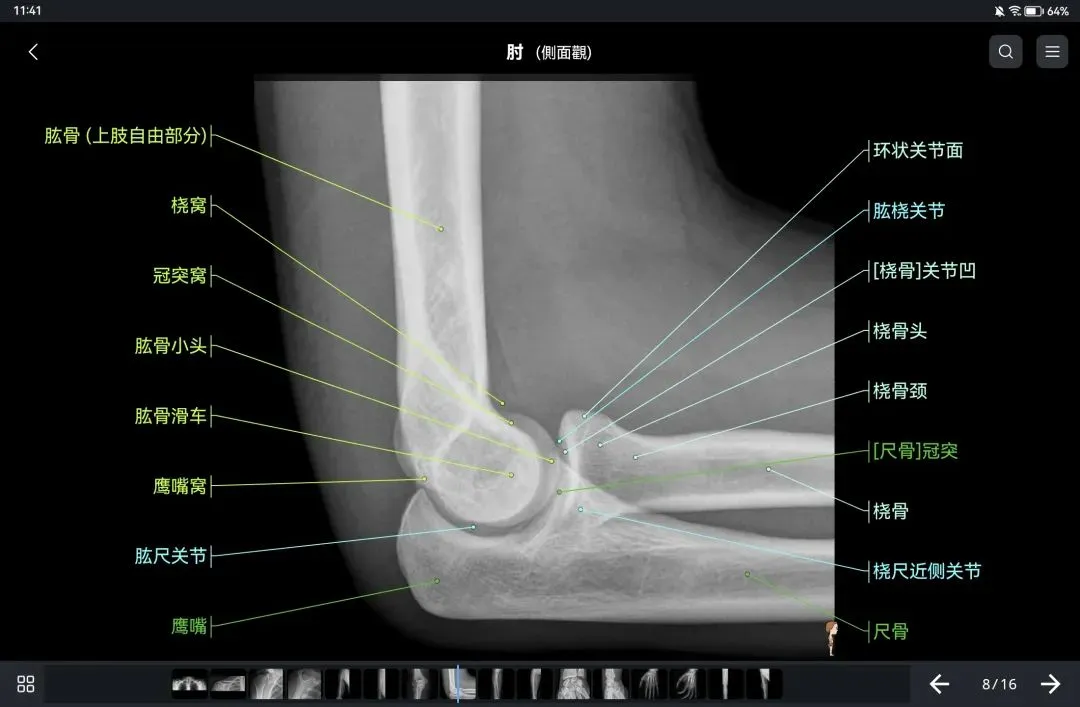

覆盖了X光、CT、MRI、断层大体解剖、核医学、介入造影、医学插图等多个模块,覆盖全身各个系统的影像解剖(正常解剖结构,无病例),其中的解剖结构高达87万个,结构标注超精细,超高清图像,历时两年研发设计完成✅。